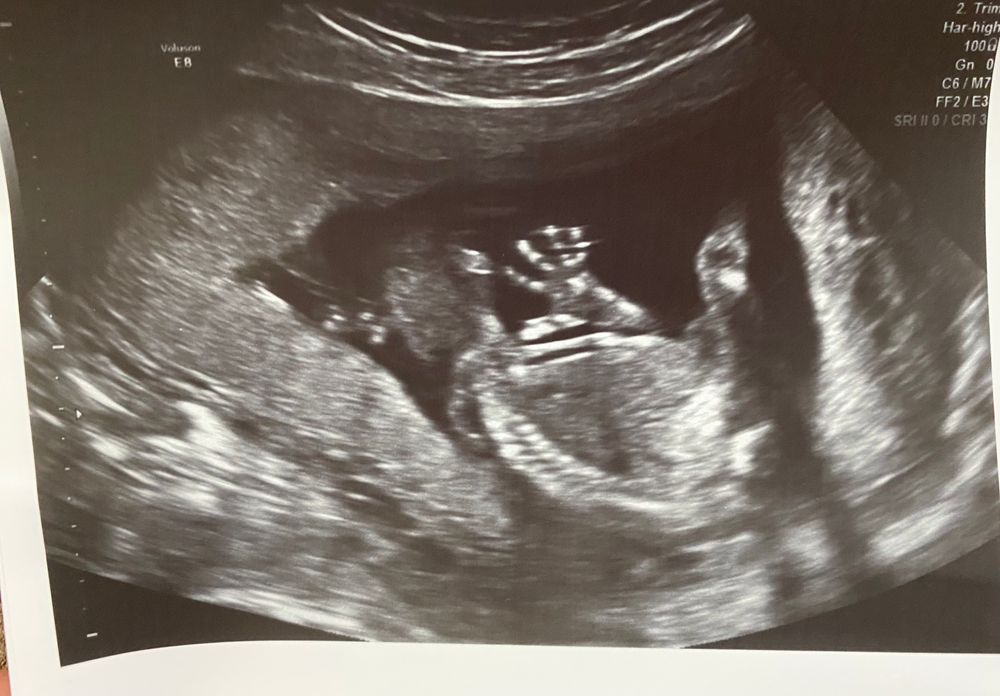

На память. Второй скрининг. Пол 🙈

Пошла наша 21 неделя, сегодня была на скрининге. В итоге у нас не мальчик, а девочка. Такие дела 😃💓

Развивается согласно сроку, все хорошо, слава Богу. Весим мы почти 400 грамм. Шейка 35 мм.

Активничает, пинается вовсю))) плацента наконец поднялась ,я очень переживала из-за этого